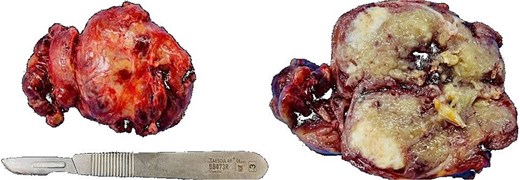

An exploratory surgery was performed, during which a well-encapsulated retroperitoneal mass was identified near the pancreas. The mass was completely removed with preservation of surrounding structures (Fig. 3). Gross examination showed a 60 × 45 × 35 mm yellow–gray encapsulated mass with scattered calcified foci (Fig. 4).

Intraoperative view of the retroperitoneal mass after complete surgical excision (indicated by arrow).

Gross specimen showing a 60 × 45 × 35 mm encapsulated, yellow–gray mass with scattered calcifications.